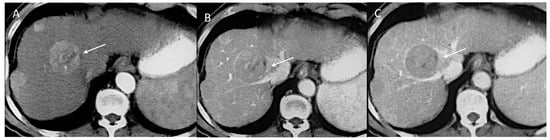

2.2.3. HCC Diagnosis

2.2.4. Ancillary Features